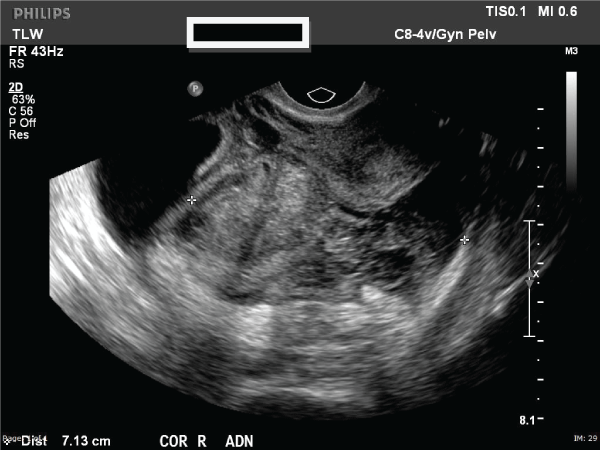

At presentation, her vital signs were unremarkable and she was alert and in no acute distress. On physical examination, her abdomen was soft, non-distended with mild tenderness in the right lower quadrant. Her laboratory evaluation was remarkable for a serum β-hCG of 80mIU, hemoglobin of 9.4g/L and hematocrit of 28.9%. Ultrasonography revealed a 10cm adnexal mass of unknown etiology and small free fluid collection in the lower pelvis (Figure 1). The mass was noted to be heterogenous, multilobulated and multicystic in nature. Computed tomography revealed no evidence of metastatic disease. Hence, a serum cancer antigen 125 level was measured and found to be 44IU/mL. The patient was transferred to our institution for concerns of neoplastic etiology of this adnexal mass. Upon arrival, she continued to be hemodynamically stable and was admitted to the Gynecology ward and consented for diagnostic laparoscopy, possible right salpingo-oopherectomy, removal of adnexal mass, possible laparotomy and other indicated procedures with both Gynecologic Oncology and Pathology available for expected intraoperative consultation. In the operating room, diagnostic laparoscopy revealed extensive adhesions of bowel loops to the anterior and lateral abdominal wall, obscuring the pelvis. Based on the extensive adhesive disease, the decision was made to proceed with exploratory laparotomy via a midline vertical incision. After abdominal adhesioloysis was performed, a 10x6cm unruptured right hematosalpinx was exposed and a right salpingo-oopherectomy was performed in order to remove the mass in its entirety (Figure 2). The specimen was sent for frozen section analysis and was noted to be consistent with products of conception, thus confirming the diagnosis of ectopic pregnancy. Her postoperative course was unremarkable. Eight weeks postoperatively, the patient’s β-hCG was negative and she had a normal pelvic examination.